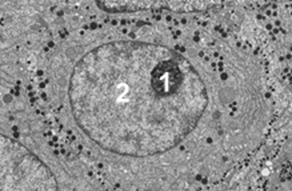

- īn microscopia electronica, īnvelisul nuclear este constituit din doua membrane trilaminate separate printr-un spatiu clar - cisterna sau spatiul perinuclear, cu o grosime de 10-15 nm. Membrana externa se continua cu membranele reticulului endoplasmatic granular, iar pe fata citoplasmatica are atasati ribozomi. Din loc īn loc, anvelopa nucleara este strabatuta de canale - porii nucleari - prin care se realizeaza pasajul macromolecular, (figurile 5 ).